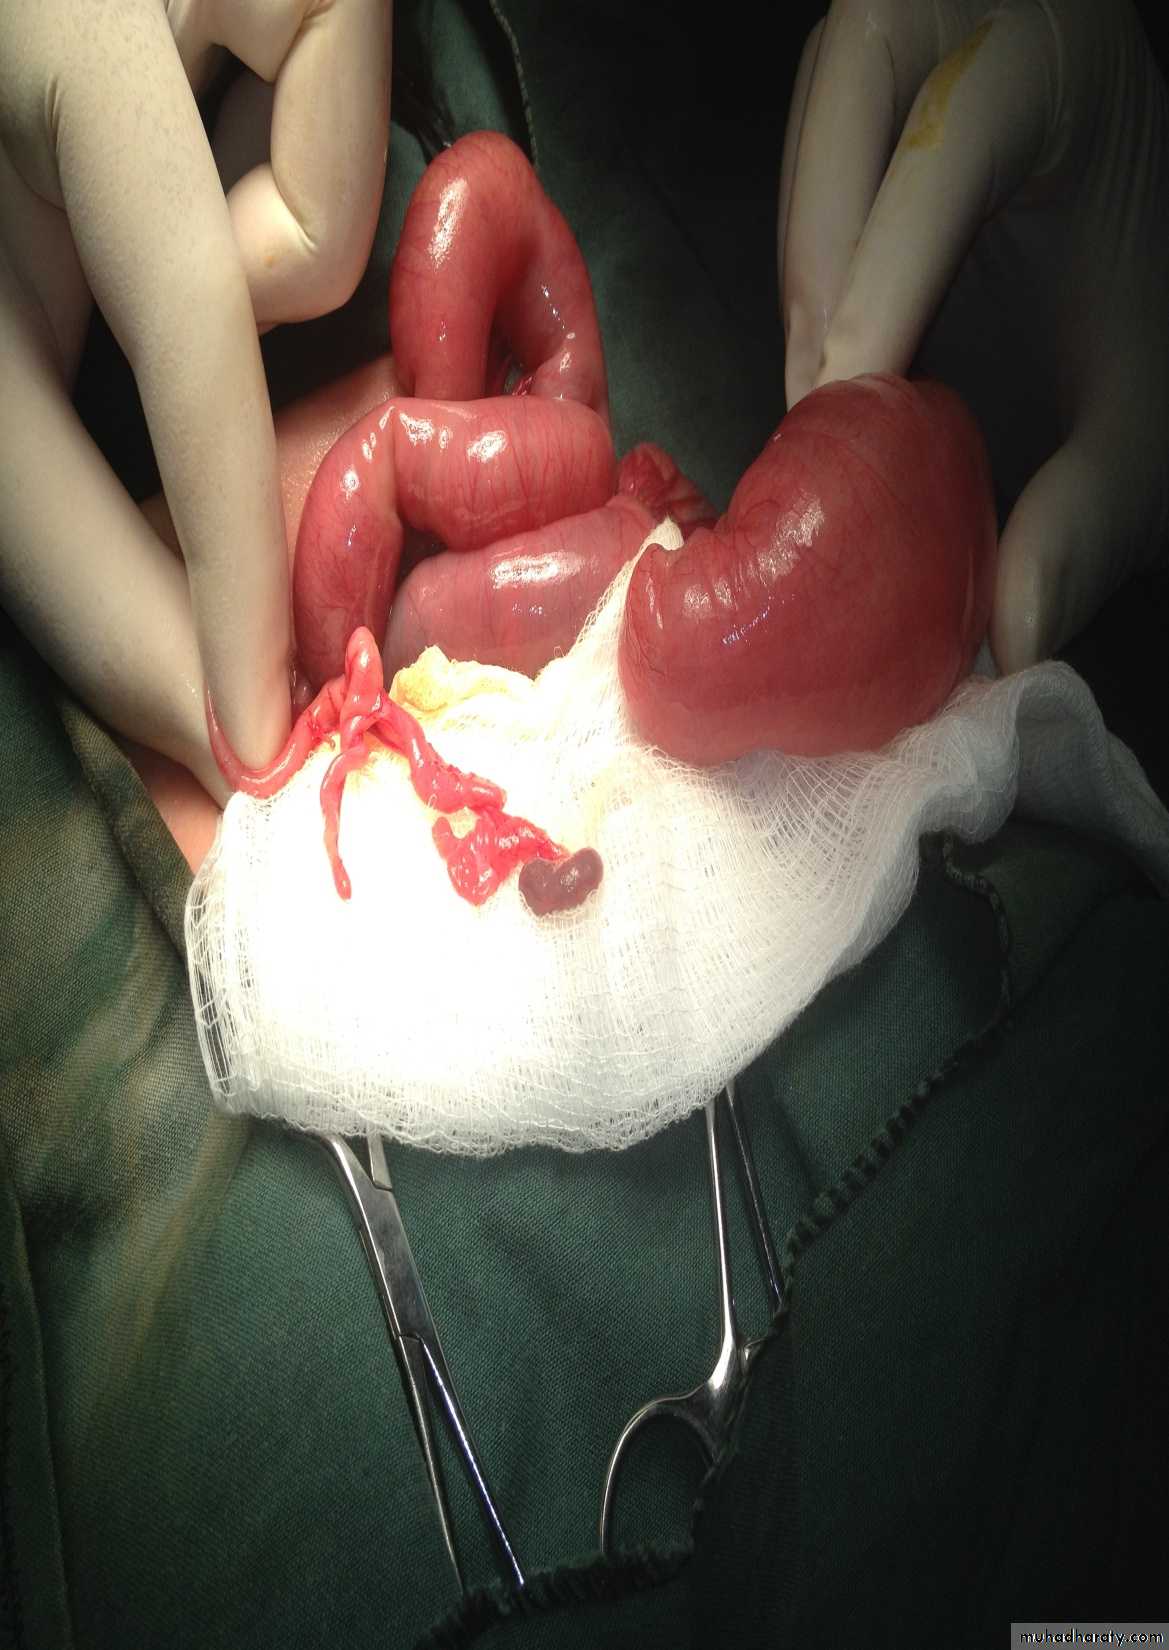

N.E.C